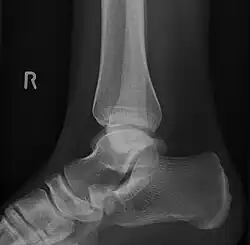

To diagnose accessory navicular syndrome, the foot and ankle surgeon will ask about symptoms and examine the foot, looking for skin irritation or swelling. The doctor may press on the bony prominence to assess the area for discomfort. Foot structure, muscle strength, joint motion and the way the patient walks may also be evaluated. X-rays are usually ordered to confirm the diagnosis. If there is ongoing pain or inflammation, an MRI or other advanced imaging tests may be used to further evaluate the condition.[5]

Radiological images